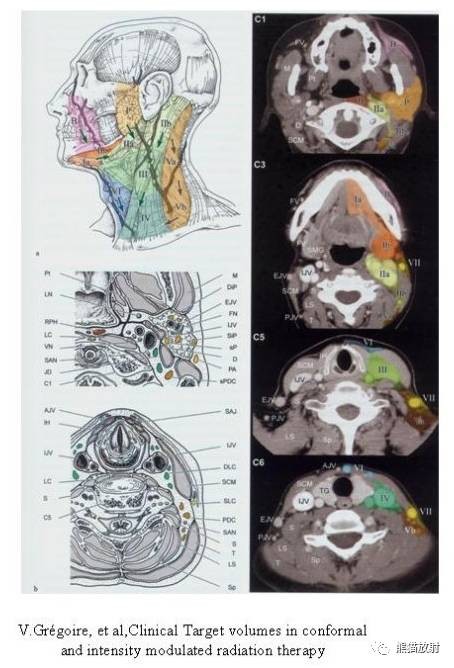

颈部淋巴结分为七区:

I区:颏下及颌下淋巴结

II区:颈内静脉链上组

III区:颈内静脉链中组

IV区:颈内静脉链下组

V区:颈后三角区淋巴结,即胸锁乳突肌后缘、斜方肌前缘及锁骨构成的三角区内的淋巴结

VI区:中央区淋巴结,包括喉前、气管前和气管旁淋巴结

VII区:上纵隔淋巴结

舌骨上水平CT增强图像

横白线在两侧颌下腺后缘。

线以前为I区淋巴结,线后为II区淋巴结。在颈内静脉附近为IIA区,颈内静脉后面不接近静脉的淋巴结为IIB区。

舌骨水平CT增强图像

横白线划在胸锁乳突肌后缘。

白线前为III区淋巴结,后为V区淋巴结。